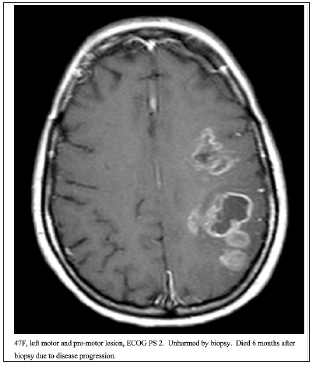

This retrospective analysis characterized the iatrogenic hemorrhage rates for stereotactic biopsy and overall survival in a large series of patients at one institution. All of these patients had unresectable high-grade gliomas, and all were managed by experienced tumor surgeons. The term “unresectable” is debatable and beyond the scope of this paper. Figures 2-4 show imaging for several patients included in this cohort. Data on outcomes for unresectable high-grade gliomas following stereotactic biopsy is very limited. We identified variables associated with increased risk of poor postoperative outcomes. Age was a strong predictor of 60-day mortality and overall survival. PS discriminated for 60-day mortality and overall survival following biopsy, but this did not reach statistical significance. Neither PS nor age had any prognostic value for risk of bleeding given our few bleeding events. Performance status is a well-established prognostic factor in patients with glioma. One previous study showed that glioblastoma patients with preoperative Karnofsky Performance Scale (KPS) ≤ 50 had a median OS of 1.8 months, while patients with KPS 60, 70, 80, and ≥ 90 had a median OS of 2.8, 4.8, 7.3, and 17.2 months, respectively (HR=1.24, 95% CI=1.06–1.44, P=0.006). The total cohort in this study was 206 patients, 93 of which who underwent surgical resection and 113 who underwent biopsy. Our series did not demonstrate PS significantly affecting prognosis, likely due to the fact that all patients in our series had unresectable lesions, and OS was very poor for the entire population. Age had the strongest effect on the risk of death within 60 days and overall survival following biopsy. Older age predicted significantly higher likelihood of death within 60 days and worse OS. This is consistent with existing literature showing that increasing age is a negative prognostic factor for glioblastoma, although there is very limited data looking at outcomes only for unresectable high-grade gliomas. Our data shows that combining PS and age provides superior prognostic information rather than age or performance status alone. We identified one subgroup that significantly outlived the other three subgroups. PS 0-2 and ≤ 65 had a much-improved median OS compared to the other groups, while PS 0-2 and age > 65, PS 3-4 and age ≤ 65, and PS 3-4 and age > 65 all had similarly very poor outcomes. The majority of studies describing the risks of stereotactic biopsy consider the morbidity and mortality directly attributable to the procedure itself. By tracking mortality within 60 days and OS, this study encapsulates patients who were harmed by the procedure and those who experienced clinical deterioration or death due to natural progression of their disease. These patients with an extremely poor prognosis likely represent a patient population for which stereotactic biopsy is at best, futile, and at worst, harmful. Our data suggests that if a patient is over 65 years old or has an ECOG PS of 3-4, their median OS is only 3 to 4 months, and these patients are likely better served with hospice care and/ or empiric radiation rather than a biopsy.

Figure 4:47F, left motor and pre-motor lesion, ECOG PS 2. Unharmed by biopsy. Died 6 months after biopsy due to disease progression.